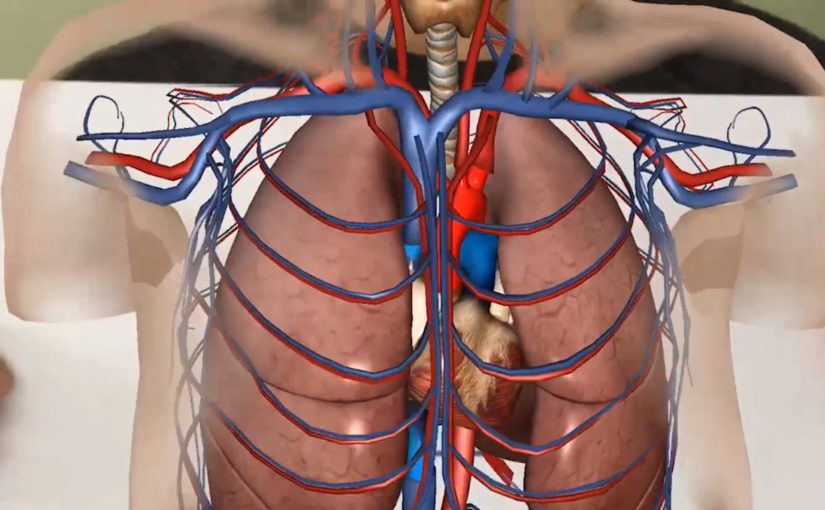

3D PROBLEMS, 2D LEARNING

Complex medical subject matter is poorly illustrated and in standard teaching materials. Also, healthcare professionals and students often struggle with conventional imagery and two-dimensional diagrams when trying to understand complex scenarios.

AR applications are ideal ways to better illustrate complex concepts. Trainees no longer have to visualize the two dimensional subject matter in 3D, the subject matter in question is represented, as it is in practice, right in front of them. While it does not replace traditional simulation, trainees can now practice without the need for individual mannequins or subject matter experts using AR. This reduces the cost, but also the man hours needed to qualify trainees.

Unlike traditional classroom teaching aids, AR applications allow trainees to manipulate the subject matter as they needed to gain the proper insights. Through engaging and interactive materials the training is remembered longer, completed quicker, and results in better on the job decision making. For subjects such as Breech Births, Chest Emergencies, and Sepsis, quickly recognizing these conditions is important to proper treatment and patient health.